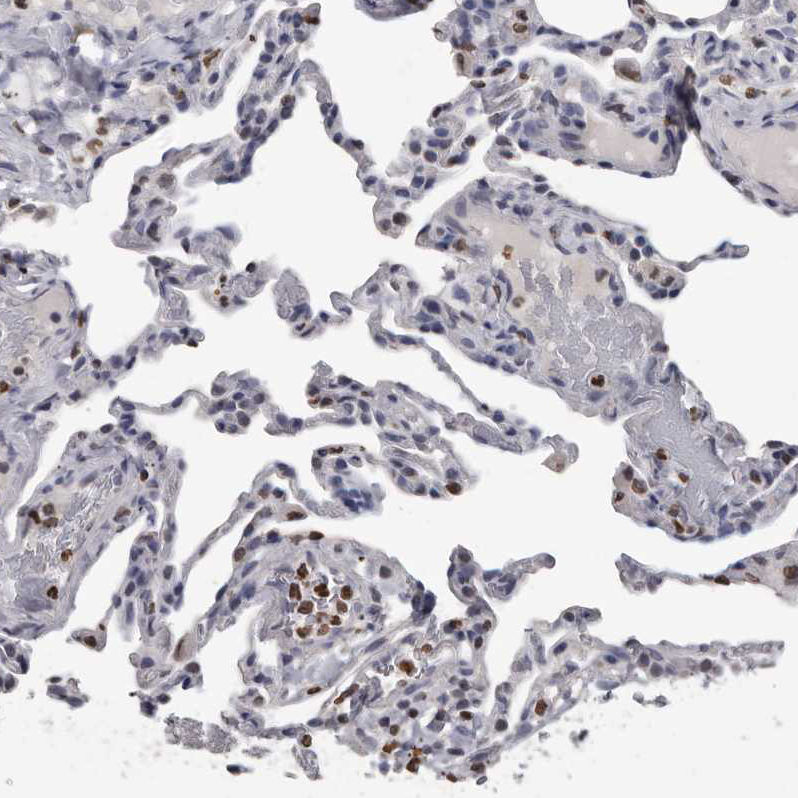

Immunohistochemistry analysis in human urinary bladder and skeletal muscle tissues using HPA029723 antibody. Corresponding AHR RNA-seq data are presented for the same tissues.